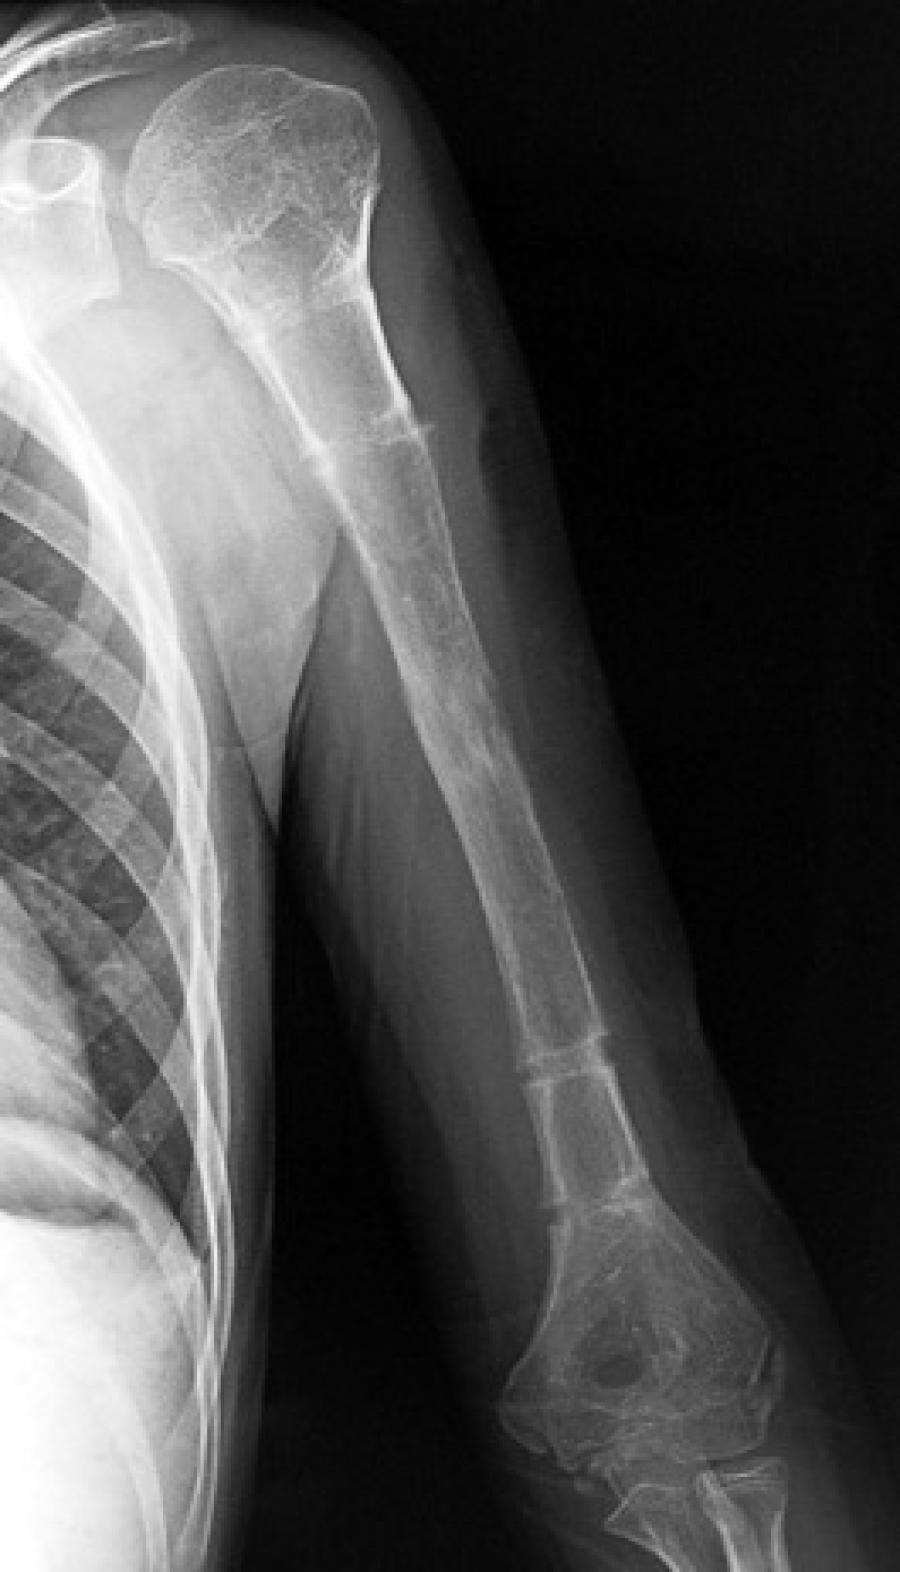

Boy uzatma ameliyatı için öncelikle kişiye boy kısalığı teşhisi konulması gerekir. Boy kısalığı tanısı için hasta öyküsü incelendikten sonra fiziksel muayene yapılarak laboratuvar değerlendirmeleri yapılır. Fiziksel inceleme aşamasında, hastanın kol ve bacakları sabit noktalar arasında mezura ile ölçülerek hem ayakta hem de yatarak hesaplamalar yapılır. Ayrıca özel boy röntgenleri ile milimetrik ölçümler gerçekleştirilir.

Klasik literatürde ameliyat başlangıç yaşı 7 olarak kabul edilse de, bazı durumlarda 2 – 3 yaşında da başlanabilir. Ameliyatın ilk seansında 10 – 15 cm, ikinci seansında 8 – 12 cm ve üçüncü seansında 8 – 10 cm arasında uzama sağlanabilir. Vücut uzuvlarının sağlıklı bir orana sahip olması için kol uzatma ameliyatı ise 14 – 16 yaş aralığında yapılarak 10 – 12 cm civarında uzama elde edilir. Kemikler 20 yaşından sonra sertleştiği için ilk seans 5 – 7 yaşında, ikinci seans 10 – 12 yaşında, üçüncü seans ise 14 - 16 yaşında yapılarak boy uzatma işlemi tamamlanır.

Boy uzatma ameliyatı, 18 yaşın üstündeki erişkinliklerde ve hastalık dışı estetik kaygılar sebebiyle de uygulanabilir. Yanlış kaynamış kırığı olanlarda, şeker hastalarında, sigara içenlerde veya kaza geçirmiş kişilerde boy kısalığı varsa, özel tekniklerle kemik düzeltilerek uzuv eşitlenmesi sağlanabilir. Kozmetik amaçlı uzatma için hastanın psikiyatrik değerlendirmeden geçmesi şarttır. Özel cihazlar ve teknikler yardımıyla günde çeyrek milim ile 1 milim arasında uzama sağlanır. Kısalık sebebi, yaş ve kemik yapısına göre toplamda 10 - 15 cm’lik uzama mümkündür. Kasların gelişimi için hastaların ameliyat sonrasında mutlaka fiziksel tedavi almaları gerekir.